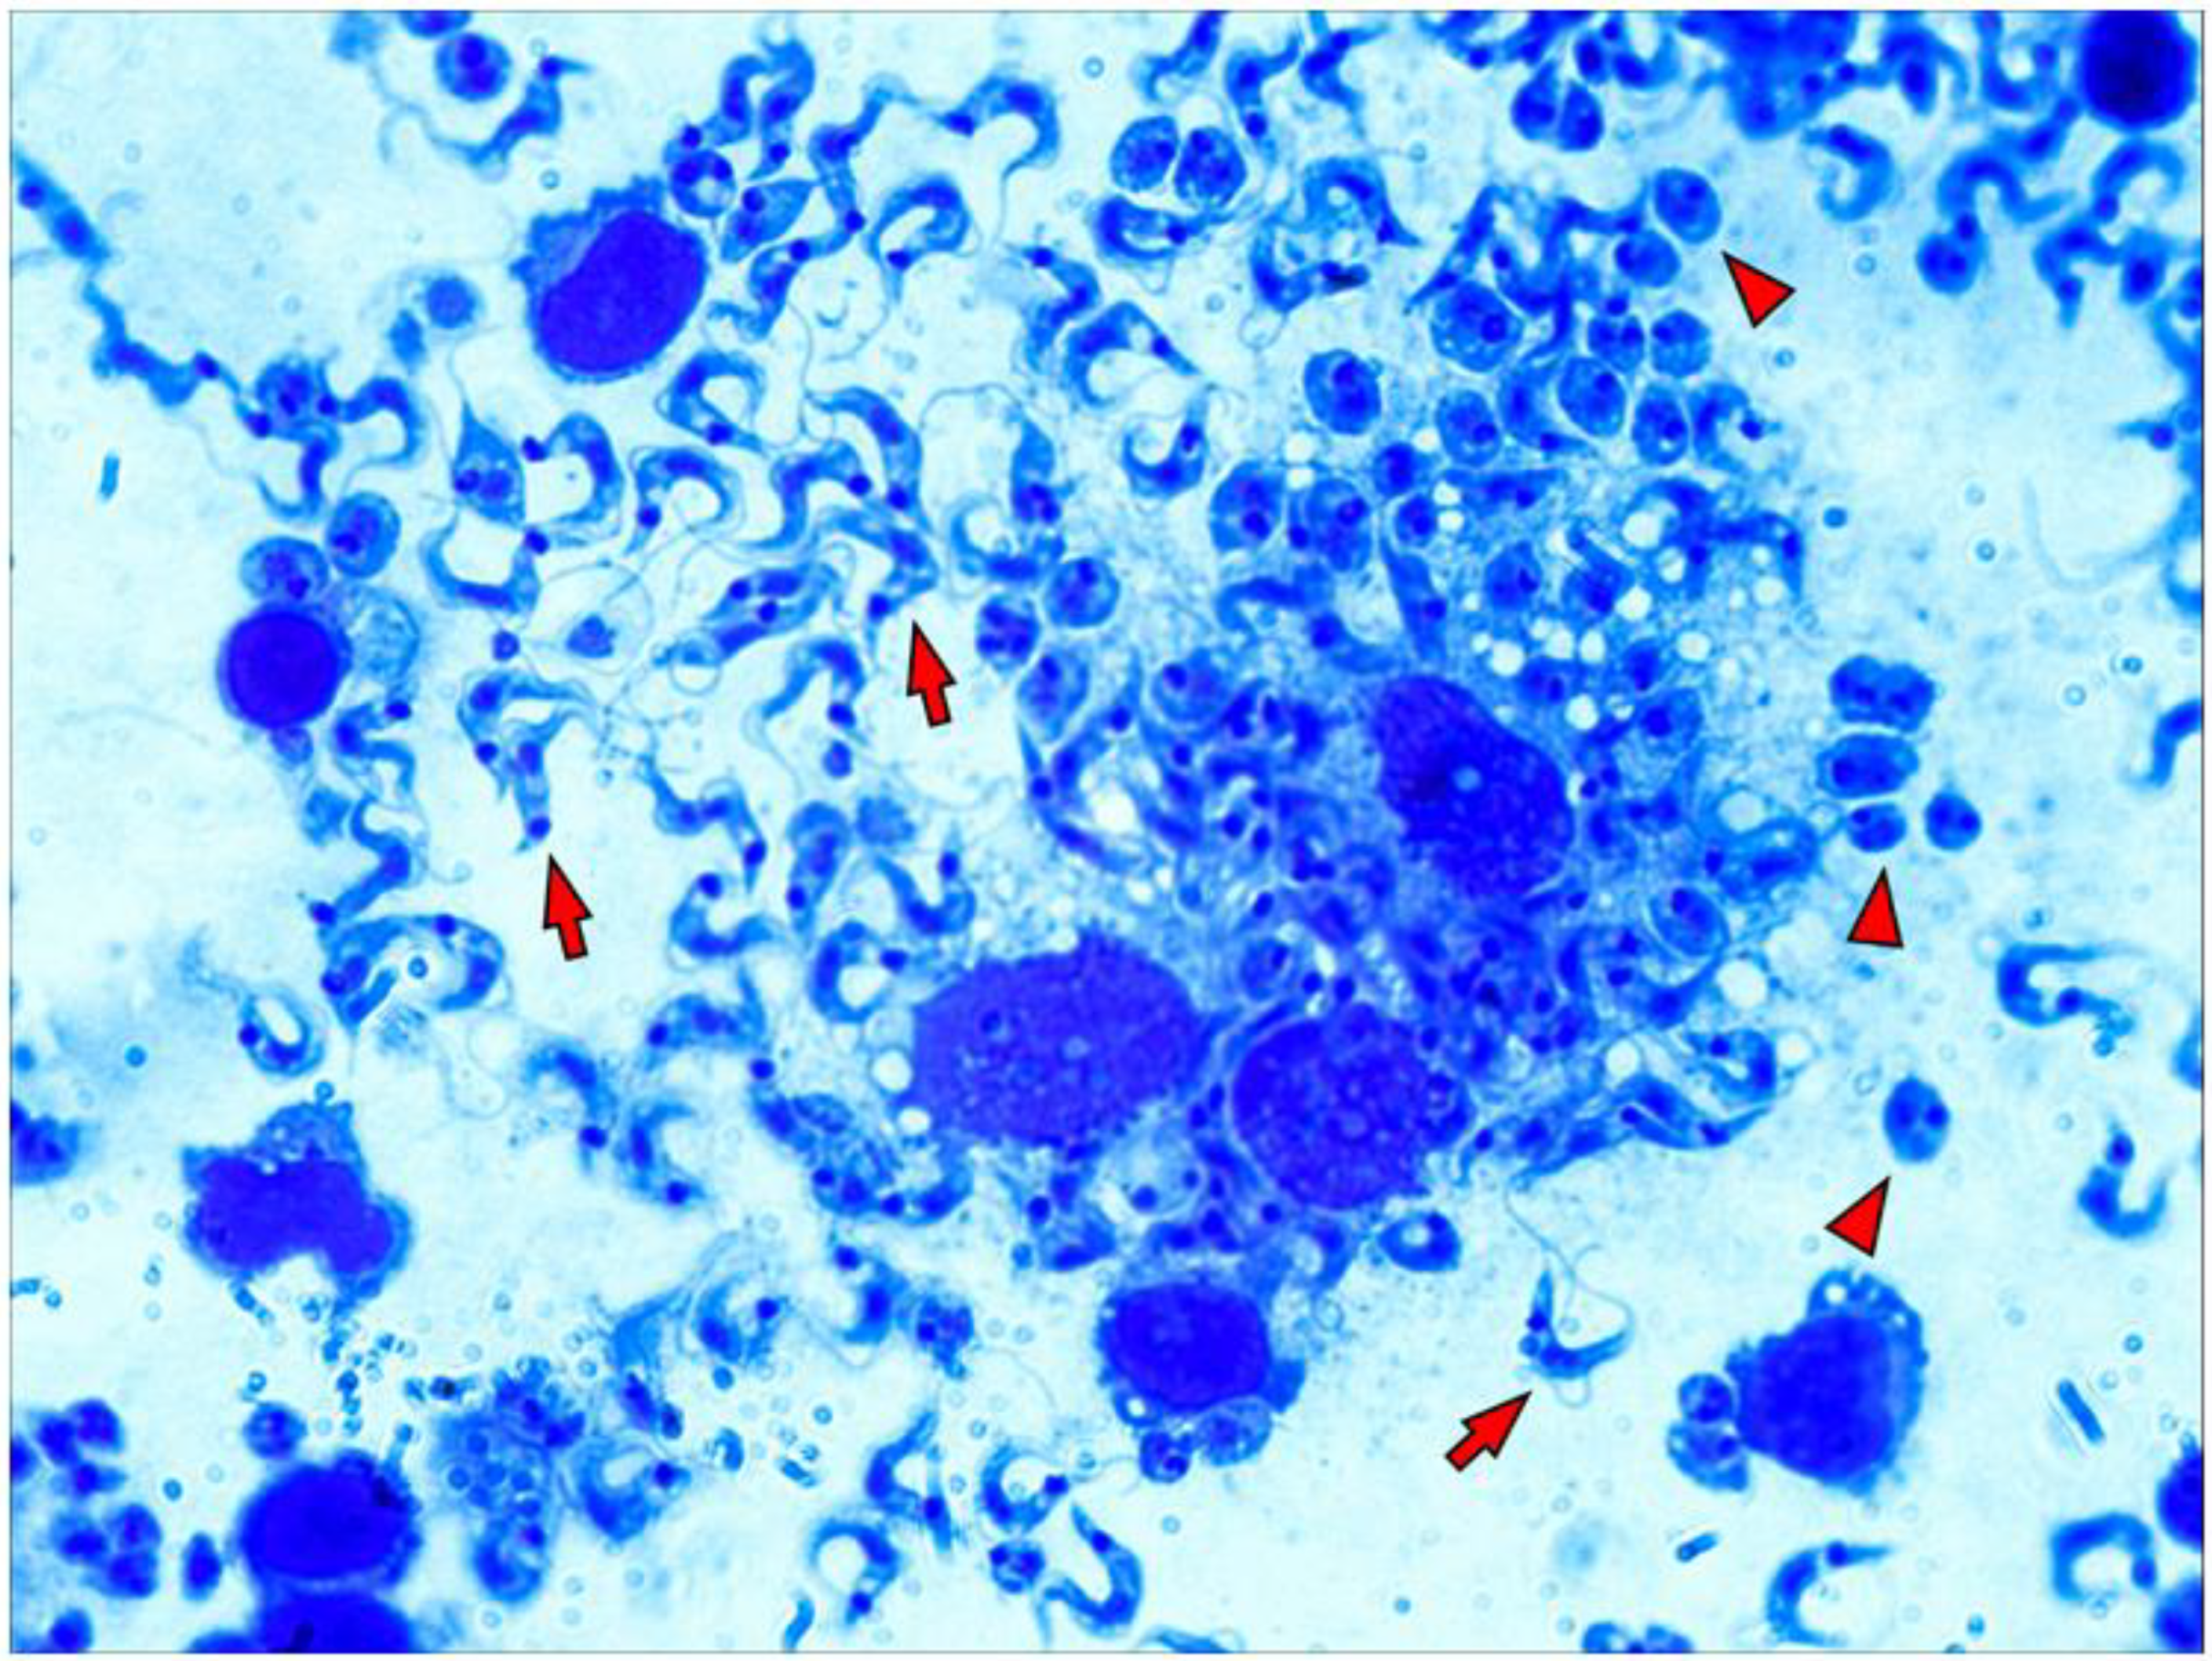

As already mentioned, amastigote forms divide intensely in the cytoplasm of the host cell, then differentiate into trypomastigotes and rupture the cell membrane. For a more detailed observation of the macrophages cultured on a 3D matrix layer infected by T. cruzi, we subjected the culture to an enzymatic digestion process with collagenase I after 96 h of infection. The suspensions obtained were used in the preparation of microscopy slides using a cytocentrifuge. The evaluation of the slides under optical microscopy showed intensely parasitized macrophages and trypomastigote forms disrupting the host cell membrane (Figure 4).

Figure 4.

Macrophages are intensely parasitized early in vitro in the 3D matrix. Peritoneal macrophages from BALB/c mice (6 × 105/well) were distributed into wells of 24-well plates covered with 3D matrix and allowed to adhere for 3 h at 5% CO2 and 37 °C. Cells were infected overnight with metacyclic forms of T. cruzi clone Dm28c in a 3:1 proportion (18 × 105). After this incubation, the wells were washed to remove non-internalized parasites. Enzymatic digestion with collagenase was performed 96 h post-infection, and the suspension obtained was used in the preparation of slides by a cytocentrifuge. The slides were fixed and stained using the Instant Prov kit (LABORCLIN) and then observed under an optical microscope (ZEISS, 100X). Trypomastogotes are indicated with red arrows, and amastigotes are indicated with red arrowheads.